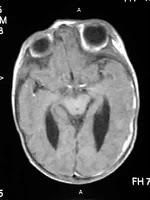

Es la dilatación del sistema ventricular del cerebro debido a un proceso

obstructivo, ya sea infeccioso, inflamatorio, neoplasico o extraventricular que impide el flujo normal

del liquido cefalorraquídeo entre el 3er y 4to ventrículo, o en la fosa

posterior del 4to ventrículo. La ventrículomegalea afecta el 0,5 de cada 1000

El diagnostico se realiza mediante ecosonografia fetal, tomografía craneal o

resonancia cerebral y su tratamiento siempre va a depender de la causa,

generalmente se utilizan analgésicos, esteroides, antibioticoterapia y

procedimientos quirúrgicos específicos.